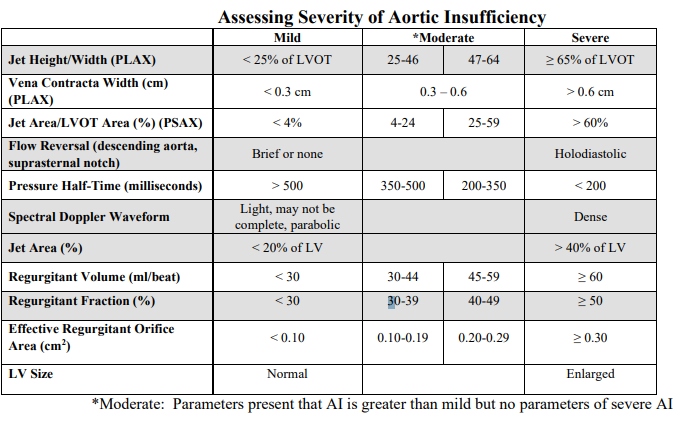

Two-Dimensional evaluation of AoV

WHAT SETTINGS

WHAT VIEWS

• Obtain careful, high resolution imaging focusing on the aortic valve in both harmonics and fundamental modes in the parasternal long axis view and short axis view

o Use magnification (zoom)